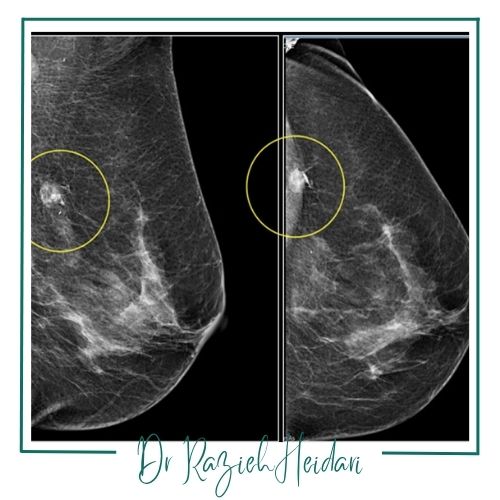

مرکز دکتر راضیه حیدری متخصص رادیولوژی با رویکردی علمی، تخصصی و بیمارمحور بهعنوان یکی از معتبرترین مراکز ماموگرافی پستان در پیروزی و شرق تهران شناخته میشود. ترکیبی از دانش روز، تجهیزات پیشرفته و تیمی از متخصصان با تجربه این مرکز را به انتخاب اول بسیاری از افراد در منطقه تبدیل کرده است.

در مرکز ژرفا از تکنولوژیهای نوین و پیشرفته مانند رادیوگرافی دیجیتال و سونوگرافی استفاده میشود که امکان تشخیص دقیق و زودهنگام بیماریها را فراهم میآورد. این تجهیزات پیشرفته بهویژه برای شناسایی بیماریها در مراحل اولیه و تودههای کوچک بسیار مؤثر هستند و به پزشکان کمک میکنند تا تصاویر واضح و دقیق از ساختارهای داخلی بدن دریافت کنند.

سهبعدی یا توموسنتز: در این روش نوین تصاویر لایهبهلایه از بافت سینه گرفته میشود که به تشخیص بهتر تودهها و کاهش موارد مثبت کاذب کمک میکند.